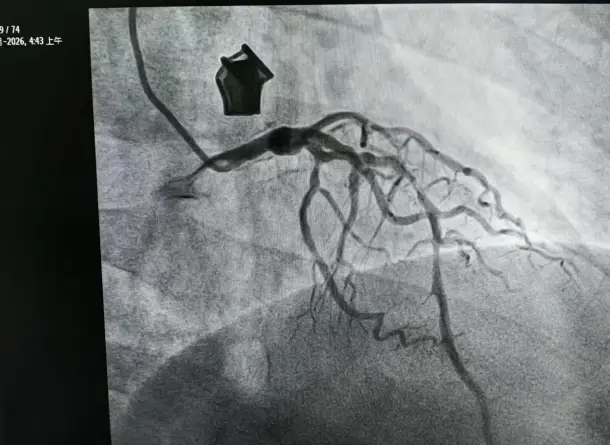

老奶奶最近常感到不舒服,来到咸阳彩虹医院内科就诊,内科副主任吕国辉接诊后,通过详细问诊、全面检查,结合临床症状,诊断老奶奶为心绞痛。为老奶奶实施冠状动脉造影检查,结果令人揪心:老奶奶冠状动脉存在重度狭窄,同时伴随严重钙化病变,血管条件极差。

术前影像检查

考虑到老奶奶冠脉钙化呈现重度弥漫性分布,且血管内超声(IVUS)检查结果显示血管壁360 度环形钙化,如同坚硬的“石质血管”,常规介入手术中,普通球囊根本无法扩张钙化严重的血管,这无疑给介入治疗带来了巨大挑战。